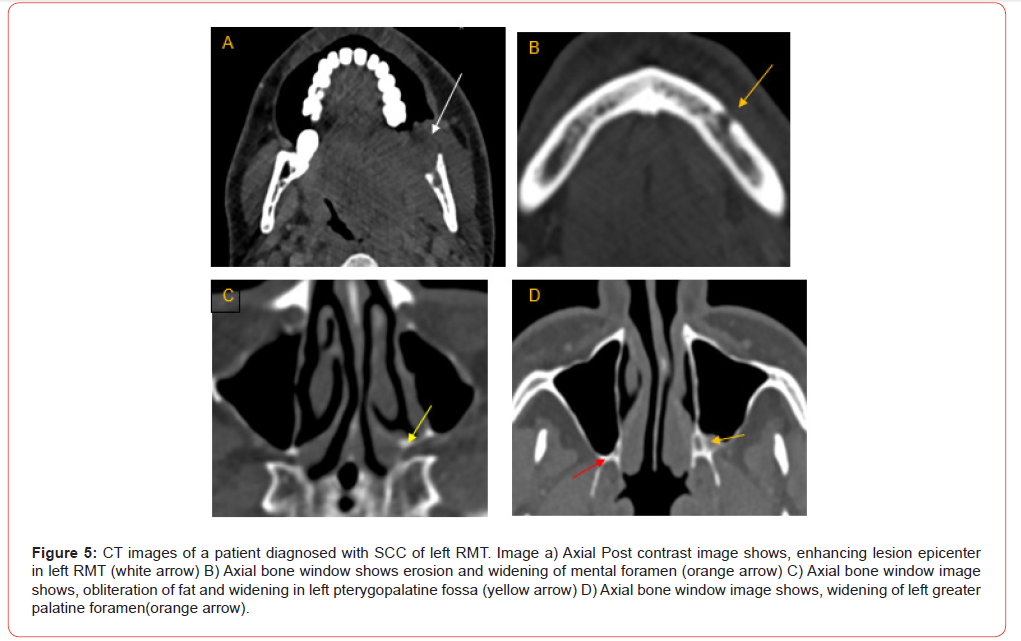

24 out of 100 patients had PNS on CT (Table 6, Figures 1-5), whereas 26 of 100 patients had histopathologically proven PNS. The two methods agreed in 88.0% of the cases and disagreed in 12.0% of the cases. There was a statistically significant agreement between the two variables, with kappa value of 0.680. Sensitivity, specificity, PPV, NPV and diagnostic accuracy of CT images for the detection of PNS were 73.1%, 93.2%, 79.2%, 90.8% and 88% respectively (Table 7). The most common nerve involved was mandibular nerve followed by maxillary nerve. Strongest predictors of PNS included foraminal widening, nerve thickening, and muscle denervation (Table 8).

Analysis of TNM staging indicated that advanced-stage tumors (III and IV) showed a higher prevalence of PNS. However, statistically, no significant relation was seen between the T and N stage of tumour and presence of PNS (Figure 6 and 7). Anatomical patterns revealed that PNS was most common in the buccal mucosa, followed by tongue, retro-molar trigone, alveolus, gingiva-buccal sulcus and hard palate (Figure 8).

The study also aimed to identify patterns of PNS involvement across different anatomical subsites. Results showed that PNS along maxillary nerve was most frequently associated with OSCC in buccal mucosa, RMT, and hard palate; while PNS along mandibular nerve was more common in OSCC affecting buccal mucosa, RMT, lower alveolus, and tongue. These patterns align with studies by Parker GD, et al. [13] and Caldemeyer KS, et al. [14] which reported that OSCC spread along mandibular and maxillary nerves often follows primary tumors in these locations. Such findings are significant for surgical planning, as they highlight specific nerve pathways that may require more intensive examination and possible resection to achieve clear margins.